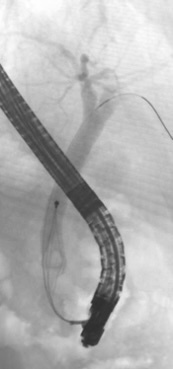

膵癌や胆管癌により胆管を閉塞する病気がある場合に行います。内視鏡を使い十二指腸にある胆管の出口から、腫瘍などにより細くなった胆管の部位にステント(ストローのような細いプラスチックの管やスプリングのような胆管を広げる金属)を挿入します。